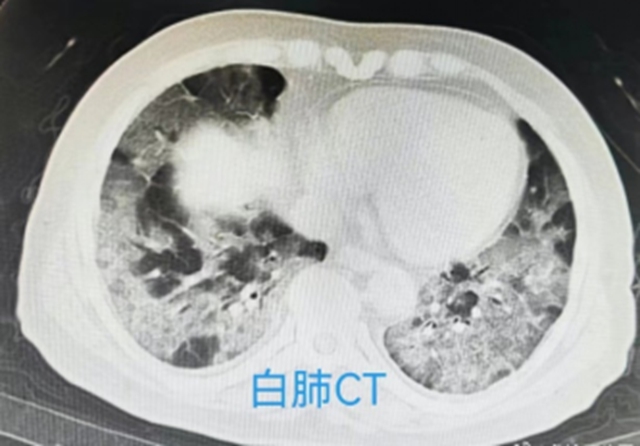

白肺是肺部影像学表现的一个口语化描述。通气功能正常的肺泡在X光和CT上都是透光的,而显示为黑色。当出现炎症和感染时,肺泡被渗出液等填充,在影像学上表现为白色。

并不是所有肺部炎症都是白肺,一般来讲,肺部炎症较重、渗出液较多,白色的影像区域面积达到70%-80%时,在临床上把它称为白肺。

“白肺”也叫急性呼吸窘迫综合征(ARDS),是指肺内、外严重疾病导致以肺毛细血管弥漫性损伤、通透性增强为基础,以进行性呼吸窘迫和难治性低氧血症为临床特征的急性呼吸衰竭综合征。临床表现为胸闷气短、呼吸不畅,血氧饱和度较低,因此会导致严重缺氧的结果。